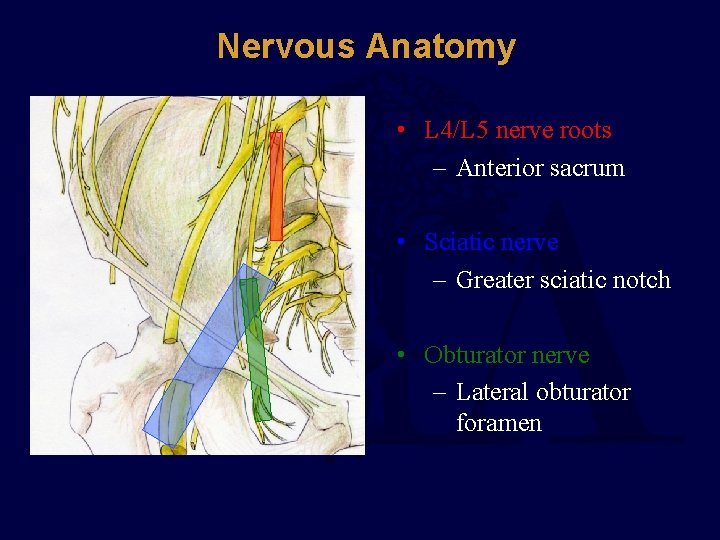

Nervous Anatomy • L 4/L 5 nerve roots – Anterior sacrum • Sciatic nerve – Greater sciatic notch • Obturator nerve – Lateral obturator foramen